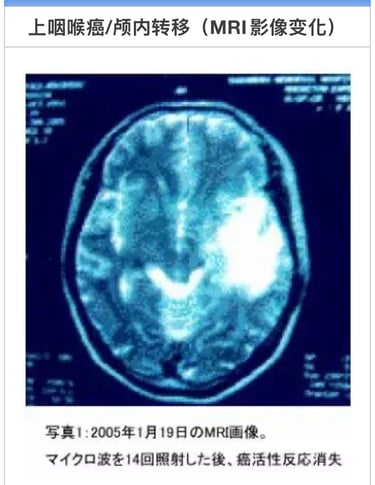

05年1月19日在脑外科被确诊左颞叶、顶叶、侧头均有转移(照片1)医生建议手术。

征得患者同意后。即于2005年1月20日开始,1天2次连续3天实施MW微波照射。之后11月、12月合计14次照射后,患者的癌症活性反应消失。

2006年1月27日的脑MRI显示肿瘤消除(照片2)。